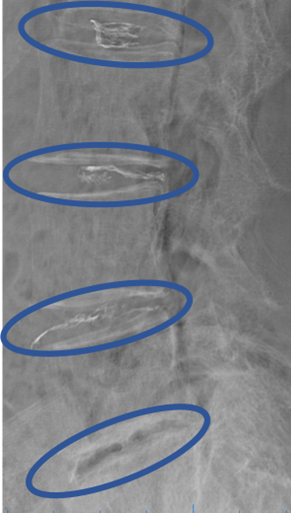

画像及び所見について

L1/2: なし

L2/3: 軽度椎間板変性

L3/4: 椎間板変性

L4/5: 椎間板変性、膨隆、繊維輪断裂

L5/S: 椎間板変性、膨隆

以上の事が画像上認められます。

L2/3、3/4、4/5、5/Sに

椎間板変性、膨隆、繊維輪断裂を認め、主症状の原因の可能性が高い。

DiscoGelを入れた後の画像になります。